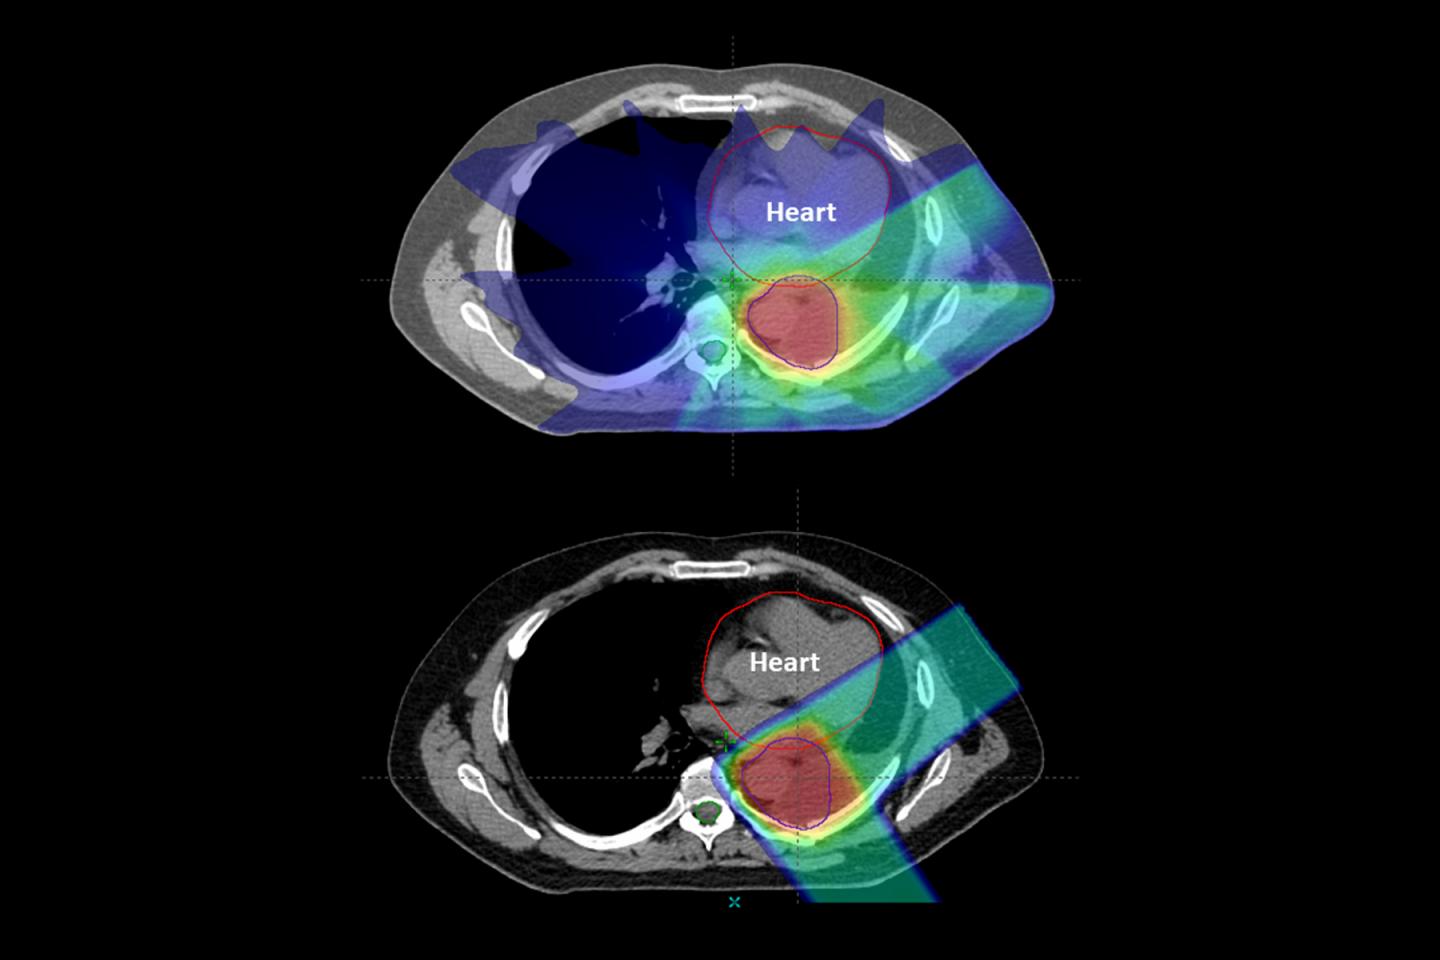

Proton therapy results in fewer side effects than traditional X-ray radiation therapy for many cancer patients, according to a new study led by Washington University School of Medicine in St. Louis and the Perelman School of Medicine at University of Pennsylvania. Even with reduced side effects, proton therapy resulted in cure rates similar to those of X-ray radiation therapy.

This study is the first large review of data across several cancer types to show a reduced side-effect profile for proton therapy compared with X-ray radiation therapy for patients receiving combined chemotherapy and radiation. Both types of radiation therapy are approved by the Food and Drug Administration for cancer treatment. Protons are relatively heavy, positively charged particles that hit their target and stop. X-ray beams consist of photons, which are much smaller particles that have almost no mass, allowing them to travel all the way through the body, passing through healthy tissue on the way out.